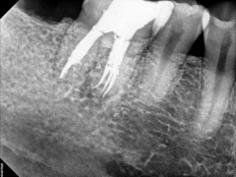

Every tooth has different numbers of roots and canal systems. With the help of magnification and high tech equipment, Dr. Jung can locate and treat the canals including MB2 on upper molars and MM on lower molars.

Among other advanced techniques and instruments utilized by our office, surgical loupes with fiber optic illumination, and the surgical operating microscope have opened up entirely new vistas for the treatment of both non-surgical and surgical endodontics. Due to the enhanced illumination and high magnification optics, calcified canals can be optimally located. Additionally, retreatment of endodontic cases that have failed due to separated instruments, separated posts, and repair of perforations can now be managed with greater efficiency and success. These cases, in the past, could be managed only by surgical approaches that had a lower success rate.